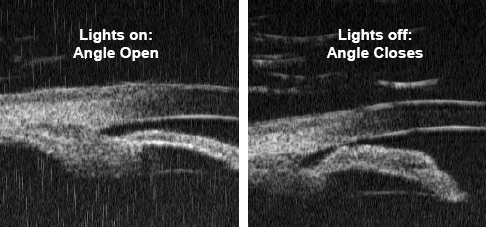

Anterior chamber angle width varies dramatically with illumination (figure and video in ref. 1) (1,2). Visible wavelength based examination methods such as gonioscopy can cause pupillary constriction and thereby open an angle in which there is irido-trabecular contact at lower light levels. The narrowest, dimmest possible slit-lamp beam with which the corneal wedge is still identifiable should be used in a fully darkened room. A 1mm long beam is sufficient and should be kept well away from the pupil.

Other subtle signs of iris-trabecular meshwork apposition such as pigment smudging (3) are useful adjuncts to direct observation of iris-meshwork contact but are no substitute for adequate examination conditions. Ultrasound biomicroscopy and newer imaging techniques such as anterior chamber ocular coherence tomography allow cross-sectional imaging without inducing miosis.